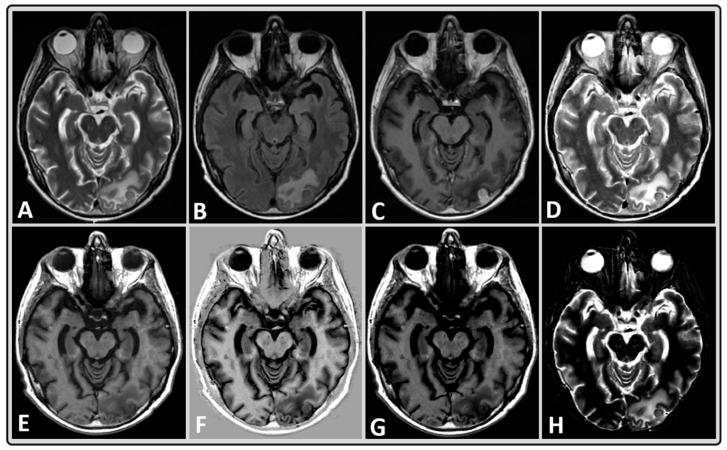

The present preliminary study aims to characterize brain metastases (BM) using T1 and T2 maps generated from newer, rapid, synthetic MRI (MAGnetic resonance image Compilation; MAGiC) in a clinical setting. We acquired synthetic MRI data from 11 BM patients on a 3T scanner. A multiple-dynamic multiple-echo (MDME) sequence was used for data acquisition and synthetic image reconstruction, including post-processing. MDME is a multi-contrast sequence that enables absolute quantification of physical tissue properties, including T1 and T2, independent of the scanner settings. In total, 82 regions of interest (ROIs) were analyzed, which were obtained from both normal-appearing brain tissue and BM lesions. The mean values obtained from the 48 normal-appearing brain tissue regions and 34 ROIs of BM lesions (T1 and T2) were analyzed using standard statistical methods. The mean T1 and T2 values were 1143 ms and 78 ms, respectively, for normal-appearing gray matter, 701 ms and 64 ms for white matter, and 4206 ms and 390 ms for cerebrospinal fluid. For untreated BMs, the mean T1 and T2 values were 1868 ms and 100 ms, respectively, and 2211 ms and 114 ms for the treated group. The quantitative T1 and T2 values generated from synthetic MRI can characterize BM and normal-appearing brain tissues.